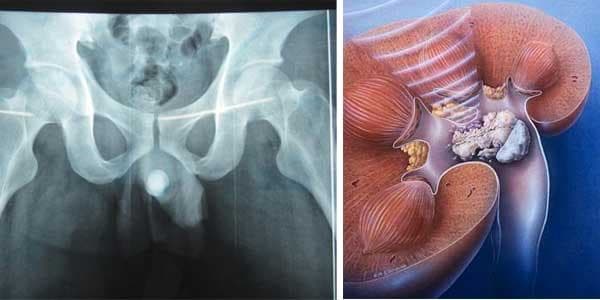

Niệu đạo là một ống dẫn nước tiểu từ bàng quang ra miệng sáo, niệu đạo nam giới đồng thời là đường đi chung của hệ tiết niệu và hệ sinh dục (khi xuất tinh). Sỏi niệu đạo chiếm khoảng 4% trong số các bệnh sỏi đường tiết niệu nói chung.

Đa số sỏi tiết niệu được hình thành từ thận, sau đó di trú theo dòng nước tiểu tới các vị trí khác của đường niệu. Sỏi gây cản trở dòng nước tiểu từ thận xuống bàng quang. Do sự tắc nghẽn này mà thận bị ứ đọng nước tiểu và gây ra các biến chứng.